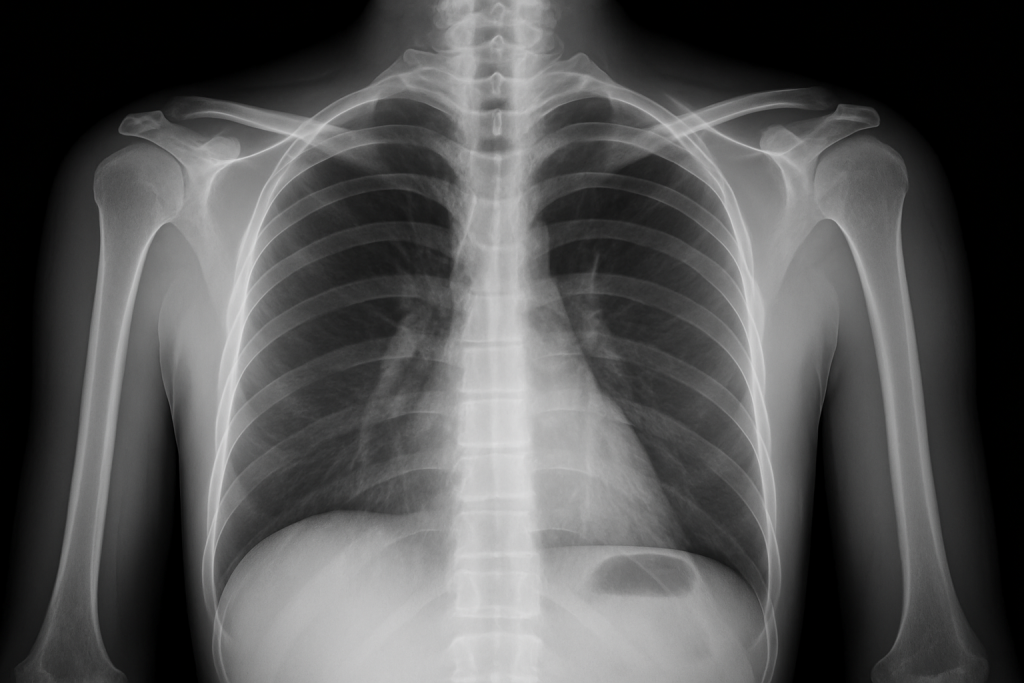

Contrairement à une photo classique, les examens d’imagerie ne capturent pas une image au sens visuel : ils traduisent des signaux physiques en images interprétables par le radiologue. La radiographie utilise les rayons X pour repérer les tissus denses comme les os. Le scanner, ou tomodensitométrie, superpose plusieurs coupes radiographiques pour obtenir une vision en 3D.

Une image à lire, pas à voir

Les images produites ne sont pas toujours évidentes à lire pour un non-initié. Ce que l’on voit, c’est une traduction codée de différences de densité, de signal ou d’écho. Les tissus se dessinent en nuances de gris ou en contrastes, mais leur interprétation dépend du contexte : un même aspect peut être normal ou pathologique selon l’âge, les antécédents, les symptômes. Le rôle du radiologue est donc central : il ne se contente pas de regarder, il analyse, compare, réconcilie l’image avec le patient. L’“image invisible” est celle de l’interprétation : c’est elle qui donne sens aux pixels. Les outils deviennent de plus en plus précis, avec des logiciels d’amplification, d’intelligence artificielle, de reconstruction 3D. Mais la lecture humaine reste irremplaçable pour contextualiser.